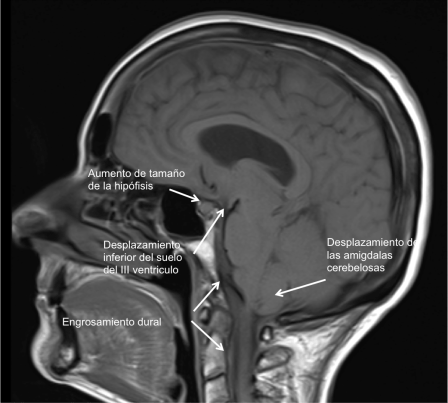

El LCR ejerce un efecto de amortiguación del contenido craneal que protege de traumatismos proporcionando además estabilidad mecánica y de sostén al encéfalo. Cuando el volumen de LCR disminuye el propio efecto gravitacional hace que el cerebro se desplace hacia abajo. Este desplazamiento es visible en la RNM cerebral y produce la tracción de estructuras sensibles al dolor que producen el habitual dolor de cabeza con la sedestación o bipedestación.

En la Imagen 1, el desplazamiento del cerebro hacia abajo produce un descenso de las amígdalas cerebelosas y del tronco cerebral que imita una Malformación de Arnold Chiari tipo I y un descenso del suelo del III ventrículo. También se observa un signo muy carácterístico que es el aumento del tamaño de la glándula hipofisaria.

En la Imagen 6 y 7, se pude observar la captación dural de contraste que se debe a la mayor concentración de contraste (gadolinio) en la vasculatura y fluido intersticial de la duramadre. Esta hipercaptación afecta a la duramadre (paquimeninge) y no a las leptomeninges (aracnoides y piamadre) por lo que no afecta a la profundidad de los surcos corticales ni alrededor del tronco cerebral, es continuo no nodular y afecta a los compartimentos supra e infratentorial. En la Imagen 1 se observa también el engrosamiento dural sin contraste en fosa posterior y primeros segmentos cervicales.